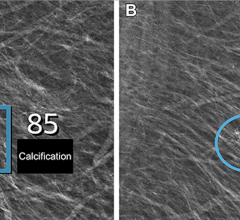

August 6, 2009 - The use of digital breast tomosynthesis and full-field digital mammography (FFDM) combined may be associated with a substantial decrease in recall rate, according to a study performed at UPMC in Pittsburgh, Penn., published in the American Roentgen Ray Society.

An estimated 10 percent of women in the United States are recalled for a second mammogram after an abnormality is detected on the first one. Some researchers believe that digital breast tomosynthesis depicts the breast tissue in a way which may allow radiologists to identify some tumors which could be missed with standard two-dimensional mammography.

In the study, 125 patients were evaluated using a combined method of digital breast tomosynthesis and standard digital mammography. The use of digital breast tomosynthesis and FFDM was associated with a 30 percent reduction in recall rate for cancer-free examinations that would have led to recall if FFDM had been used alone, reported Jules H. Sumkin, M.D., one of the authors of the study.